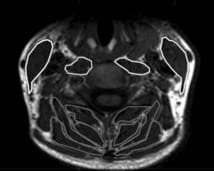

Cette revue systématique (De Pauw et al, 2016) conclue qu’il existe des preuves d’une diminution de la surface de section de coupe transversale à l’IRM des muscles fléchisseurs profonds cervicaux chez les sujets souffrant de cervicalgiques chroniques communes (Elliott et al, 2014).

Chez ces sujets, la surface de coupe des muscles extenseurs est également réduite pour les muscles sous-occipitaux (M. Rectus Capitis Maior, et M. Rectus Capitis mineurs) (Elliott et al., 2014) et les extenseurs superficiels cervicaux (Fernandez-de-las-Penas et al, 2008 ; Elliott et al, 2014). L’infiltration graisseuse des muscles cervicaux chez les patients post-wiplash est un phénomène largement décrit mais qui n’est pas retrouvé chez les sujets avec des cervicalgies chroniques communes selon cette revue (De Pauw et al, 2016).